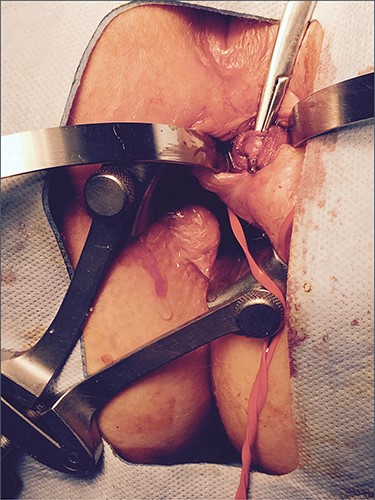

The patient was commenced on R-CHOP (Cyclophosphamide, Doxorubicin, Vincristine and Prednisone plus Rituxan), and after 3 cycles, there was a complete metabolic response on repeat PET scanning. Three months after surgery, the seton became dislodged. A repeat EUA was performed with reinsertion of the seton and an area of induration was noted between the 9 and 11 o’clock positions on the contralateral side, although without any evidence of an internal opening. The patient underwent a further 2 cycles of R-CHOP therapy. Repeat MRI confirmed the left-sided fistula with a new active tract on the right-hand side. This developed into a right perianal abscess which underwent incision and drainage. Biopsy of the right side showed no evidence of lymphoma. A left LIFT procedure was subsequently performed with ligation of the main tract in the inter-sphincteric space and a superficial secondary tract on the right side was divided and ligated. Histology showed no lymphoma. Infection in the inter-sphincteric space led to recurrence but repeat LIFT procedure plus a seton in the inter-sphincteric space resulted in closure (Fig. 5). The fistula has remained closed at 3 years of follow-up with no evidence on repeat MRI of active sepsis.